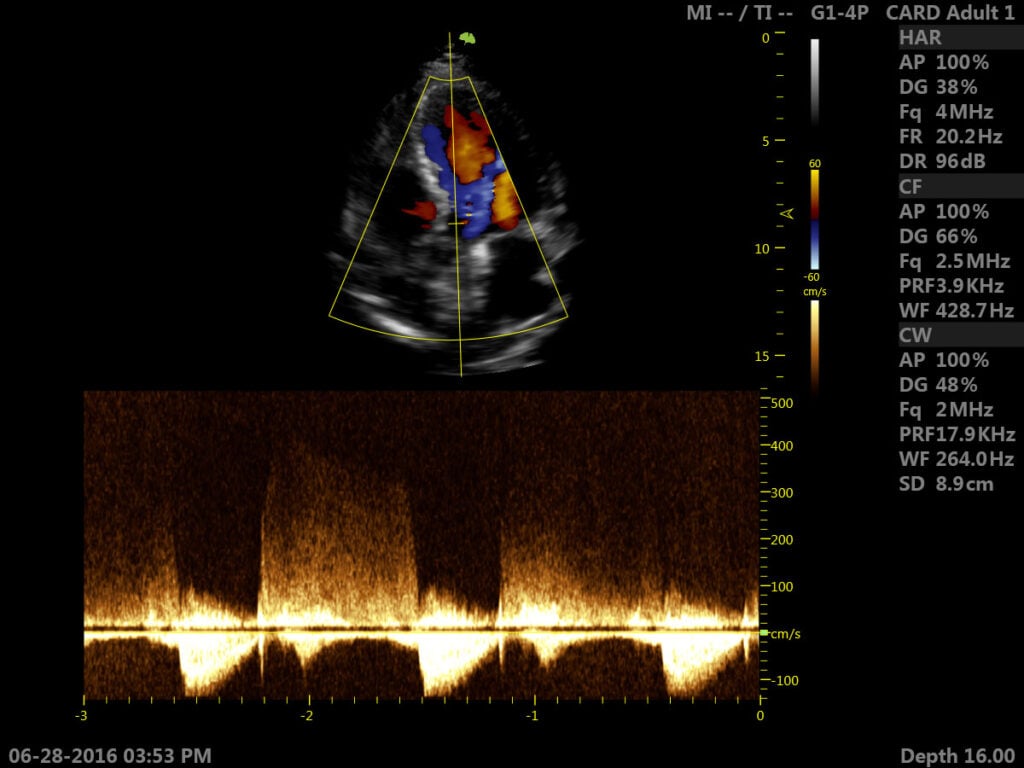

Siêu âm Doppler là một kỹ thuật siêu âm được ứng dụng rộng rãi trong siêu âm thai kỳ và siêu âm tim mạch do có thể đo được dòng chuyển động trong mạch máu. Khi siêu âm Doppler, các bác sĩ có thể phát hiện sớm và chính xác các dị tật bẩm sinh ở thai nhi, cũng như tình trạng phát triển của thai nhi trong bụng mẹ. Đặc biệt, phương pháp này cho ra kết quả chẩn đoán dị tật tim thai. Hiện nay, trên thị trường có hai loại siêu âm Doppler là siêu âm xung và siêu âm Doppler liên tục. Đây là kỹ thuật giúp chẩn đoán an toàn cho cả thai phụ, thai nhi và kể cả những thai phụ ở 3 tháng cuối thai kỳ.

Siêu âm tim là một trong những kỹ thuật sử dụng sóng siêu âm để nghiên cứu về cấu trúc cũng như đưa ra các chẩn đoán của bệnh lý ở tim. Các tín hiệu từ đầu dò sẽ phản chiếu cho thấy rõ sự co bóp của tim đang hoạt động. Ngoài ra, các bác sĩ còn có thể đánh giá về vị trí, tư thế và kích thước buồng tim hiện tại. Từ đó, sẽ phát hiện ra những lỗ khuyết trong các vách ở ngăn tim, cùng các u xơ, dị tật ở ngoài màng tim hoặc bên trong tim. Một số kỹ thuật được ứng dụng rộng rãi hiện nay có thể kế đến như:

- Siêu âm Doppler.